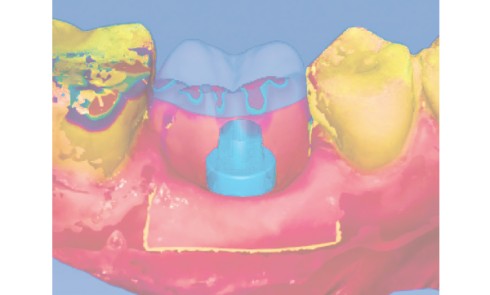

Article réservé à nos abonnés Avantages du pilier de cicatrisation anatomique personnalisé par CFAO dans le protocole d’implantation immédiate

Le point positif de l’extraction-implantation immédiate (EII) est d’abord la réduction du nombre de procédures chirurgicales et du temps de...